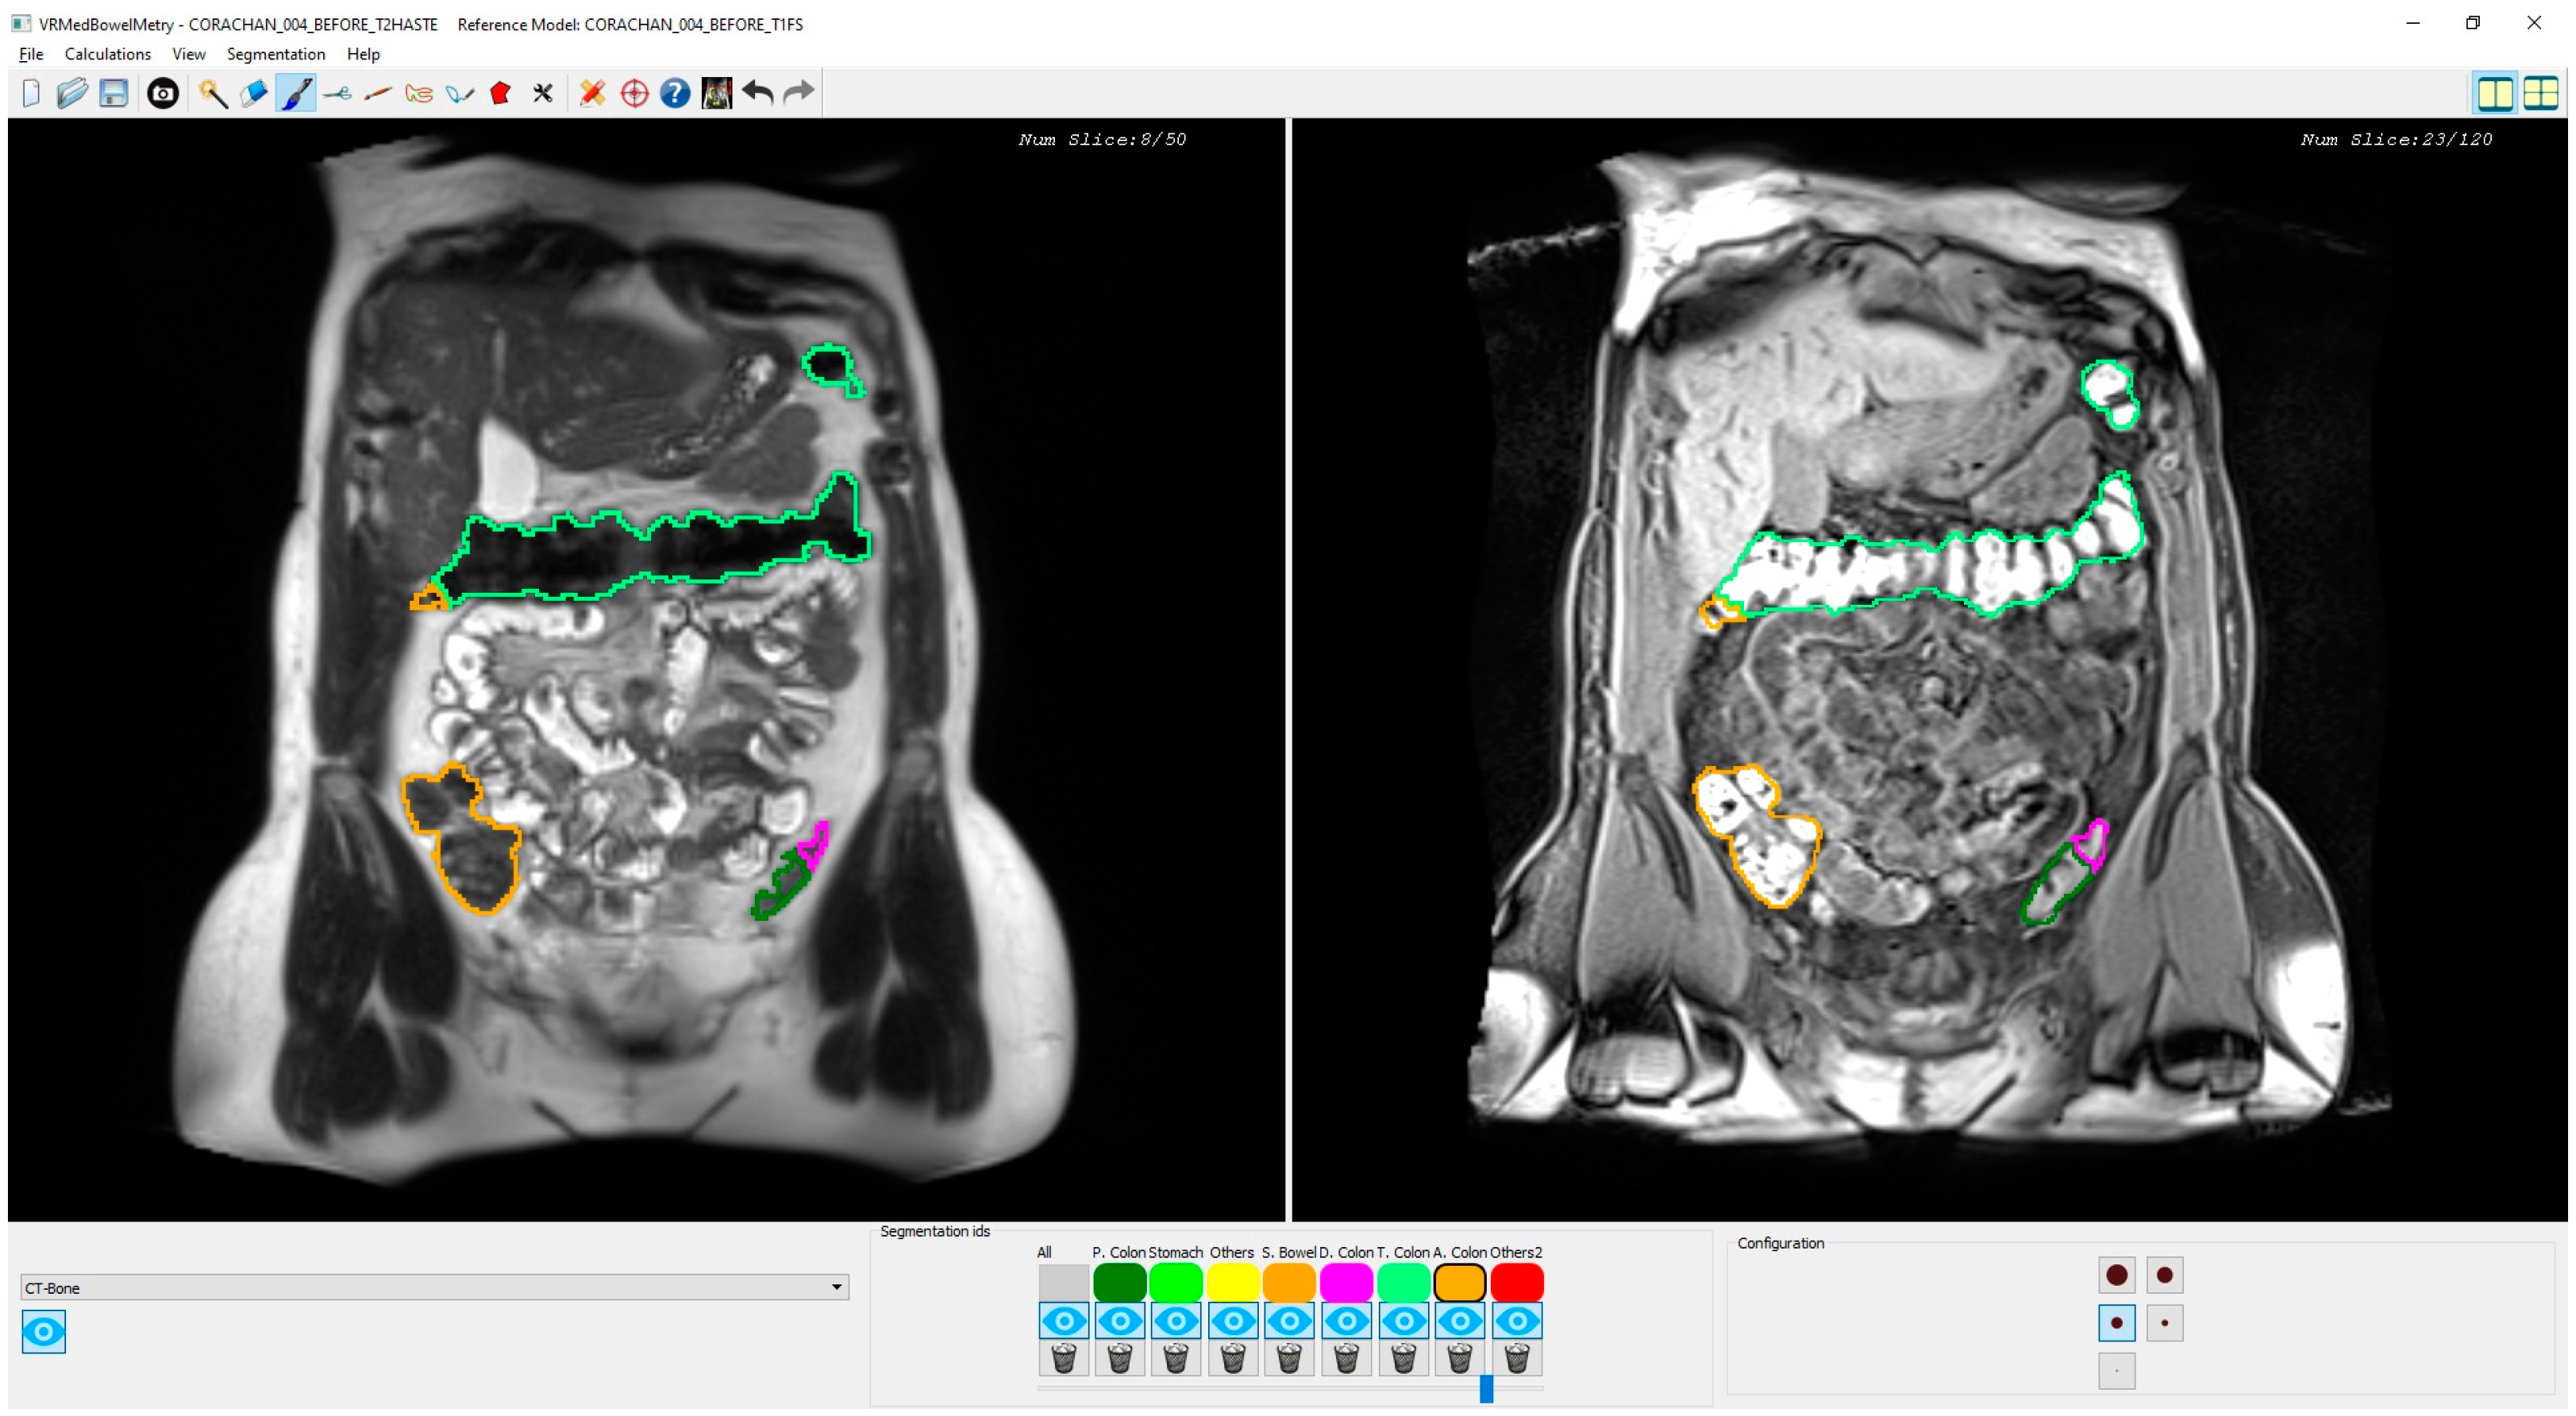

Figure 3.

Snapshot of the synchronized T2 and T1-FS module. On the left side, an original T2 image is shown with the colon segmentation outlined using a different color for each segment. On the right side, the same visualization scheme is used with its corresponding original T1-FS image.

2.3. Synchronized T2 and T1-FS Inspection

As mentioned in Section 1, there may be confusing areas of the colon that require the simultaneous visualization of both modalities to understand the colonic anatomy. Therefore, once both segmentations have been computed, their simultaneous visualization and inspection allows the specialist to analyze, validate, and, if it is needed, to correct the results.

To achieve this, we used the non-rigid registration transformation computed in Section 2.2 to obtain the spatial correspondence between T2 and T1-FS images. Specifically, given a point P in a T2 image, we can compute its correspondence point in the T1-FS space as: PT1−FS = RegisterTrans fT2→T1−FS(P). Similarly, from a point P in a T1-FS image, its correspondence point in the T2 space is: PT2 = RegisterTrans fT1→FS-T2(P).

Figure 3 shows a snapshot of the application interface in which two T2 and T1-FS synchronized images of a segmented colon are visualized in two different windows. Every time the specialist clicks on a pixel of one image (T2 or T1-FS) the system automatically computes its corresponding pixel position in the other image (T1-FS or T2) by transforming the pixel position using the formula previously presented. Moreover, using the mouse wheel, the user can navigate forward and backward around the images in a synchronous fashion following the same scheme: when the specialist moves the mouse wheel on one window, both views are updated accordingly to display the same location. The window directly affected by the wheel is moved proportionally to the wheel displacement, whereas the movement of the other window has to be calculated using the transform previously presented.

The main novelty of this inspection functionality is that, to our knowledge, it is the first one able to allow synchronous navigation of both MRI sequences considering the deformation suffered in the acquisition process. Note that the original MRI images are visualized without altering them, but the interactive navigation allows computing the corresponding image using the non-rigid transformation matrix. Moreover, the synchronized inspection facilitates a 3D mental reconstruction of the colon in both MRI modalities, which is helpful to validate the segmentation result in both sequences, and the medical expert can modify the colon segmentation, if needed, either in T2 or T1-FS independently. The 3D simultaneous visualization of both segmentations is also possible. However, performing corrections in the 3D space is quite complex and medical specialists prefer the 2D synchronized visualization of T2 and T1-FS images since it provides detailed information about the anatomical structures around the colon and facilitates the validation of the boundaries in the automatically generated segmentations.